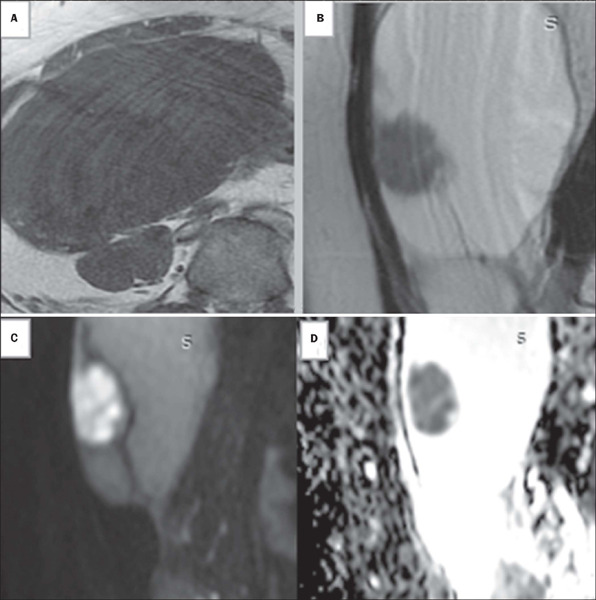

目的:探讨磁共振成像(MRI)对超声不确定卵巢及附件肿块分类的准确性。材料和方法:这是一项回顾性横断面研究,对243例共336例附件和卵巢肿块的未增强骨盆MRI扫描进行了回顾性研究。结果:未增强MRI的敏感性为97.7%,特异性为86.4%,准确率为93.8%。ROC曲线下面积为0.944 (95% CI: 0.913 ~ 0.974)。结论:我们的研究结果表明,非增强MRI方案可以用于对附件肿块进行分类,特别是在静脉注射钆造影剂不安全的临床环境中,应避免使用。

Objective: To investigate the accuracy of magnetic resonance imaging (MRI) in classifying sonographically indeterminate ovarian and adnexal masses.

Materials and methods: This was a retrospective cross-sectional study of the unenhanced pelvic MRI scans of 243 patients with a collective total of 336 adnexal and ovarian masses.

Results: Unenhanced MRI showed a sensitivity of 97.7%, a specificity of 86.4%, and an accuracy of 93.8%. The area under the ROC curve was 0.944 (95% CI: 0.913-0.974).

Conclusion: Our results show that an unenhanced MRI protocol can be used to classify adnexal masses, especially in clinical settings in which the intravenous administration of gadolinium-based contrast is not safe and should be avoided.